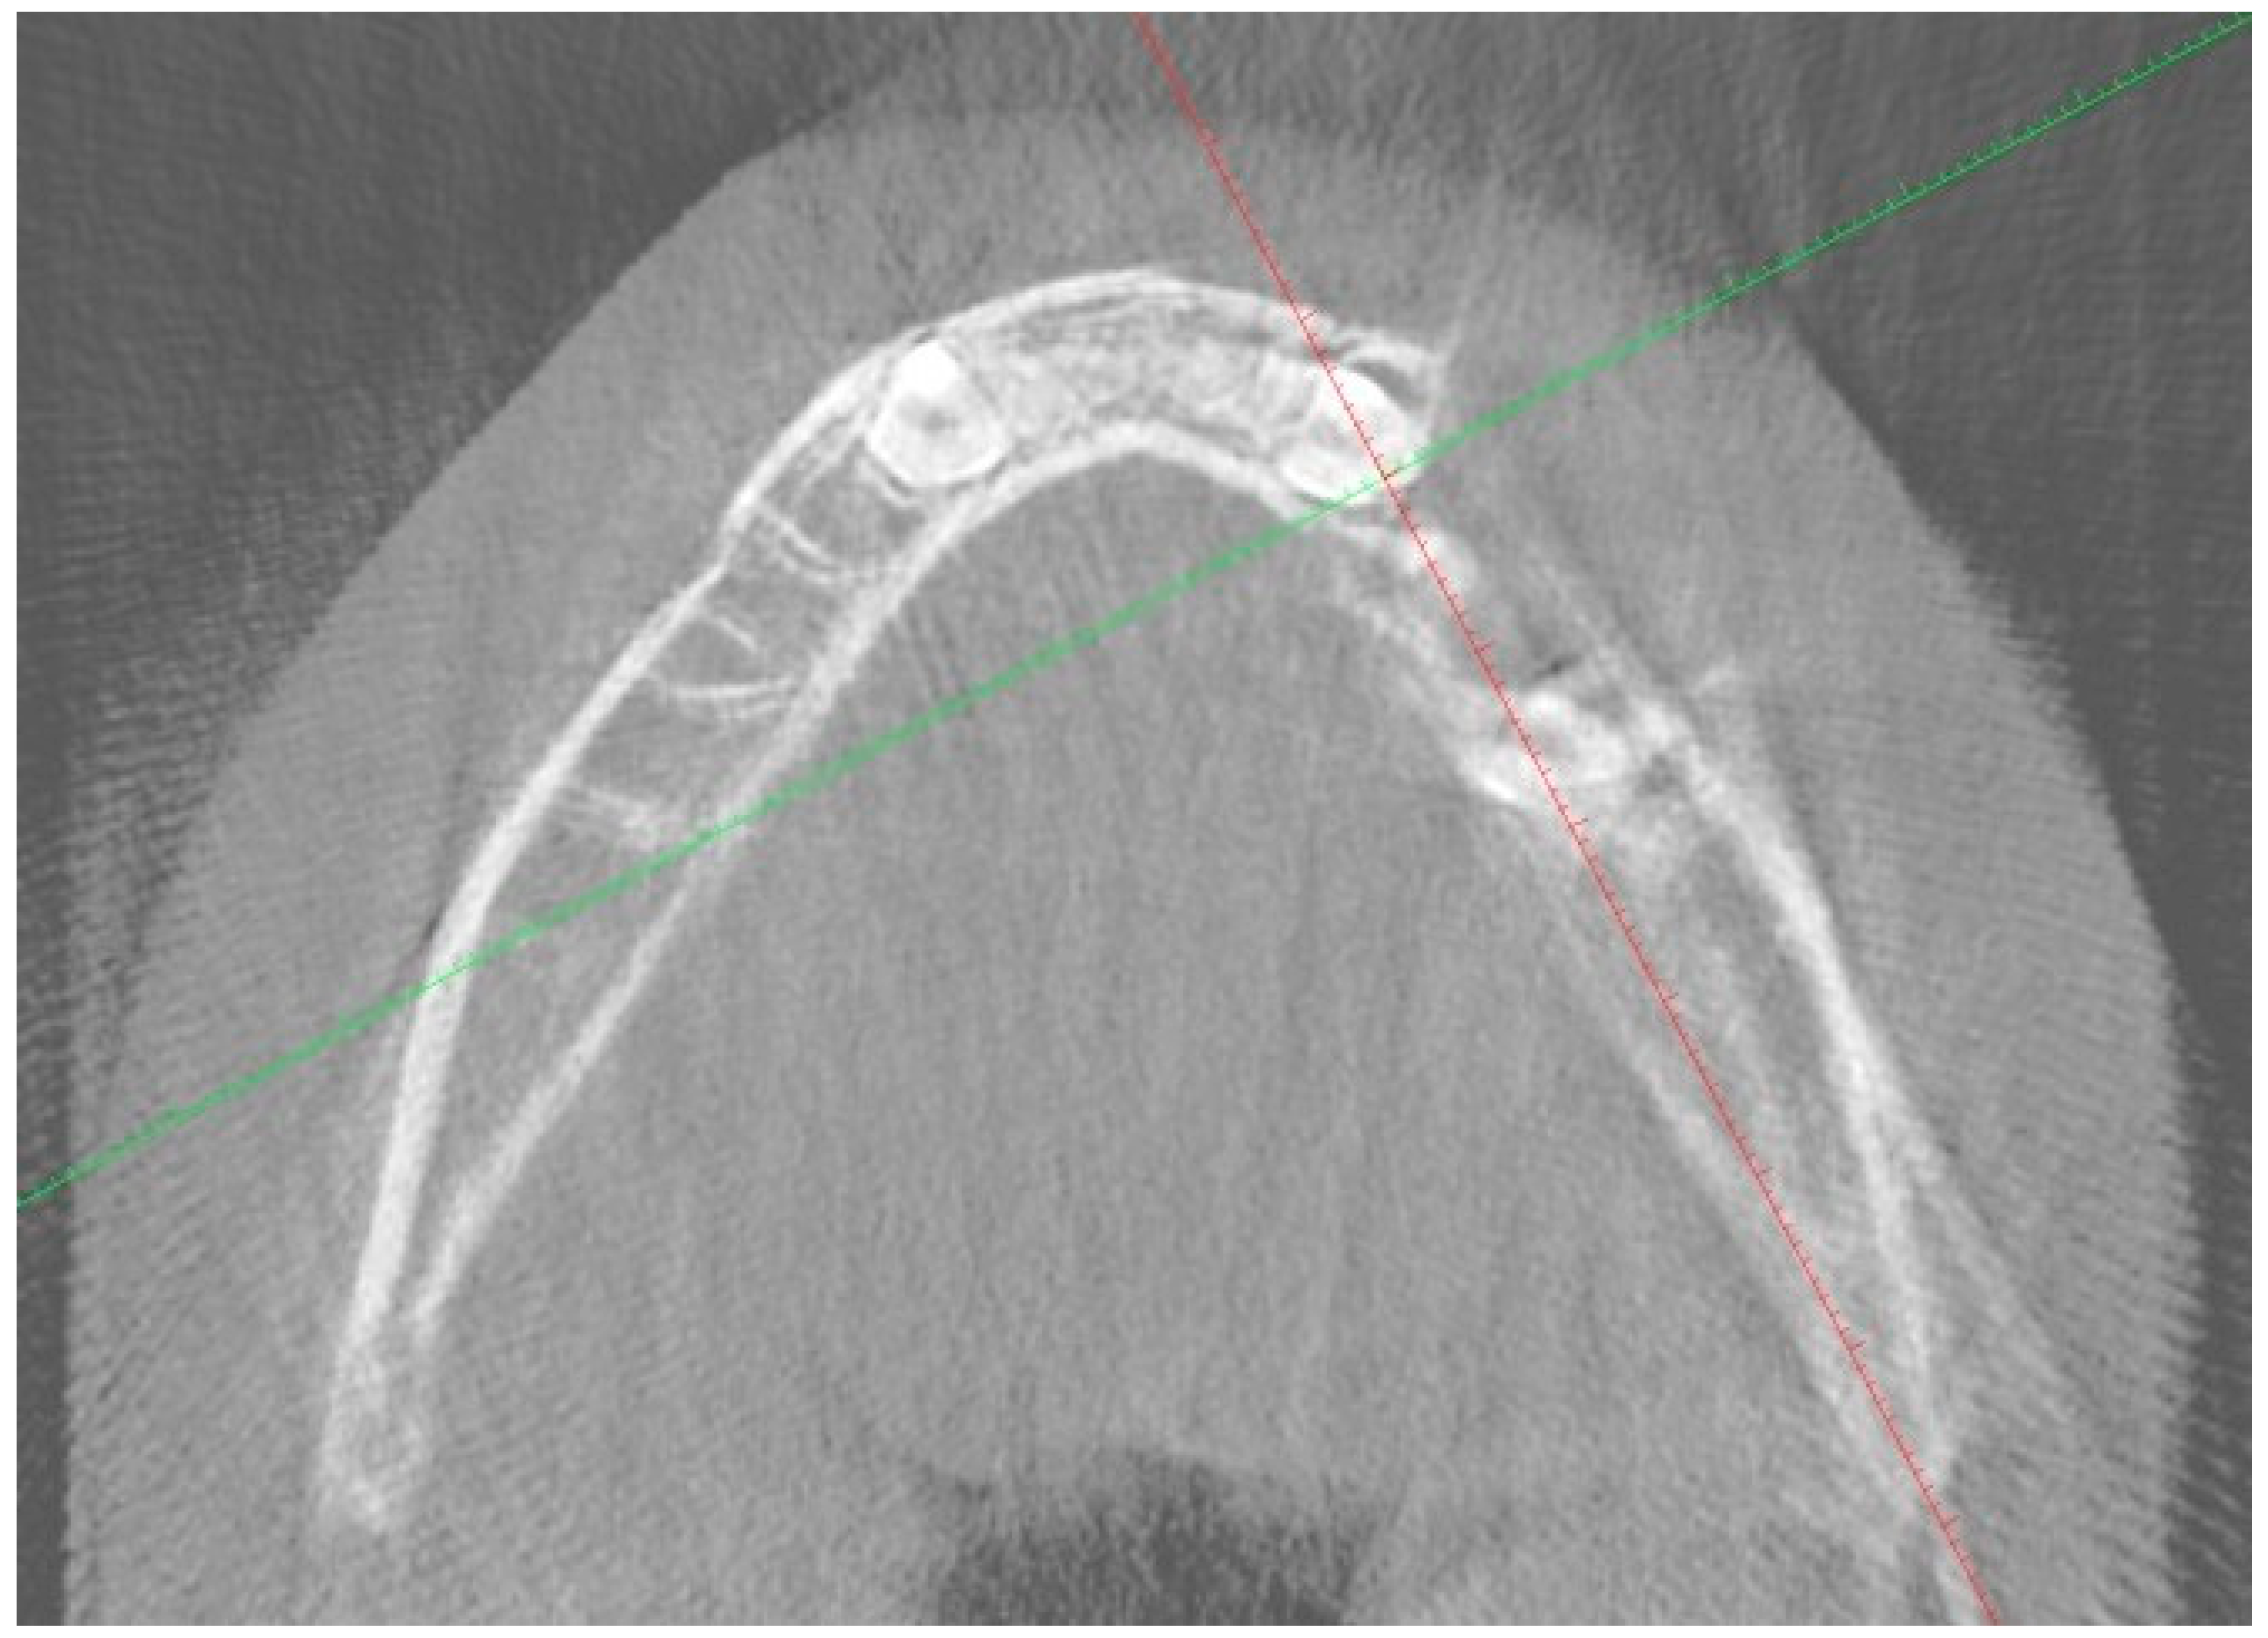

2. Case Report

3. Follow-Up and Outcomes